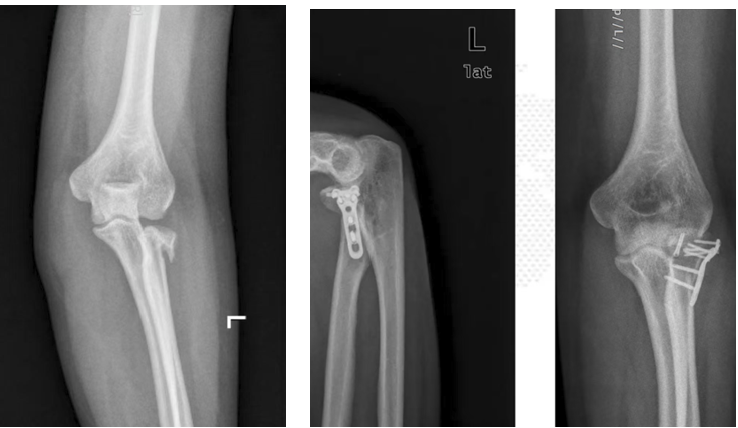

手术中切除粉碎性桡骨头及安装的桡骨头假体

手术后X线示桡骨头安放位置良好